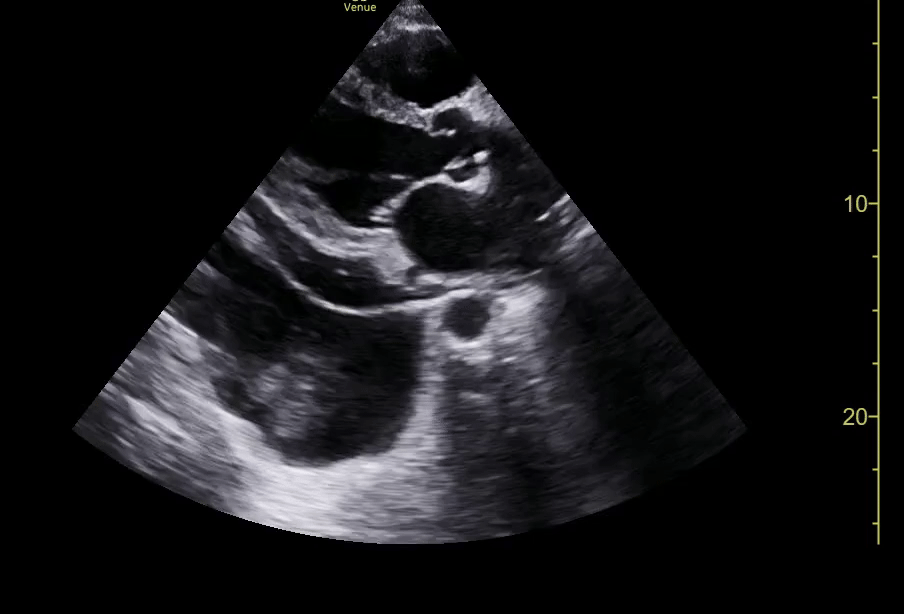

Pericardial and Pleural Effusions

Pericardial Effusion

Pacer Lead Migration

Mitral Valve Prolapse

Left Atrial Mass

Complete Heart Block

Atrial Flutter

Supine vs Left Lateral Decubitus

Normal 4 View Echo